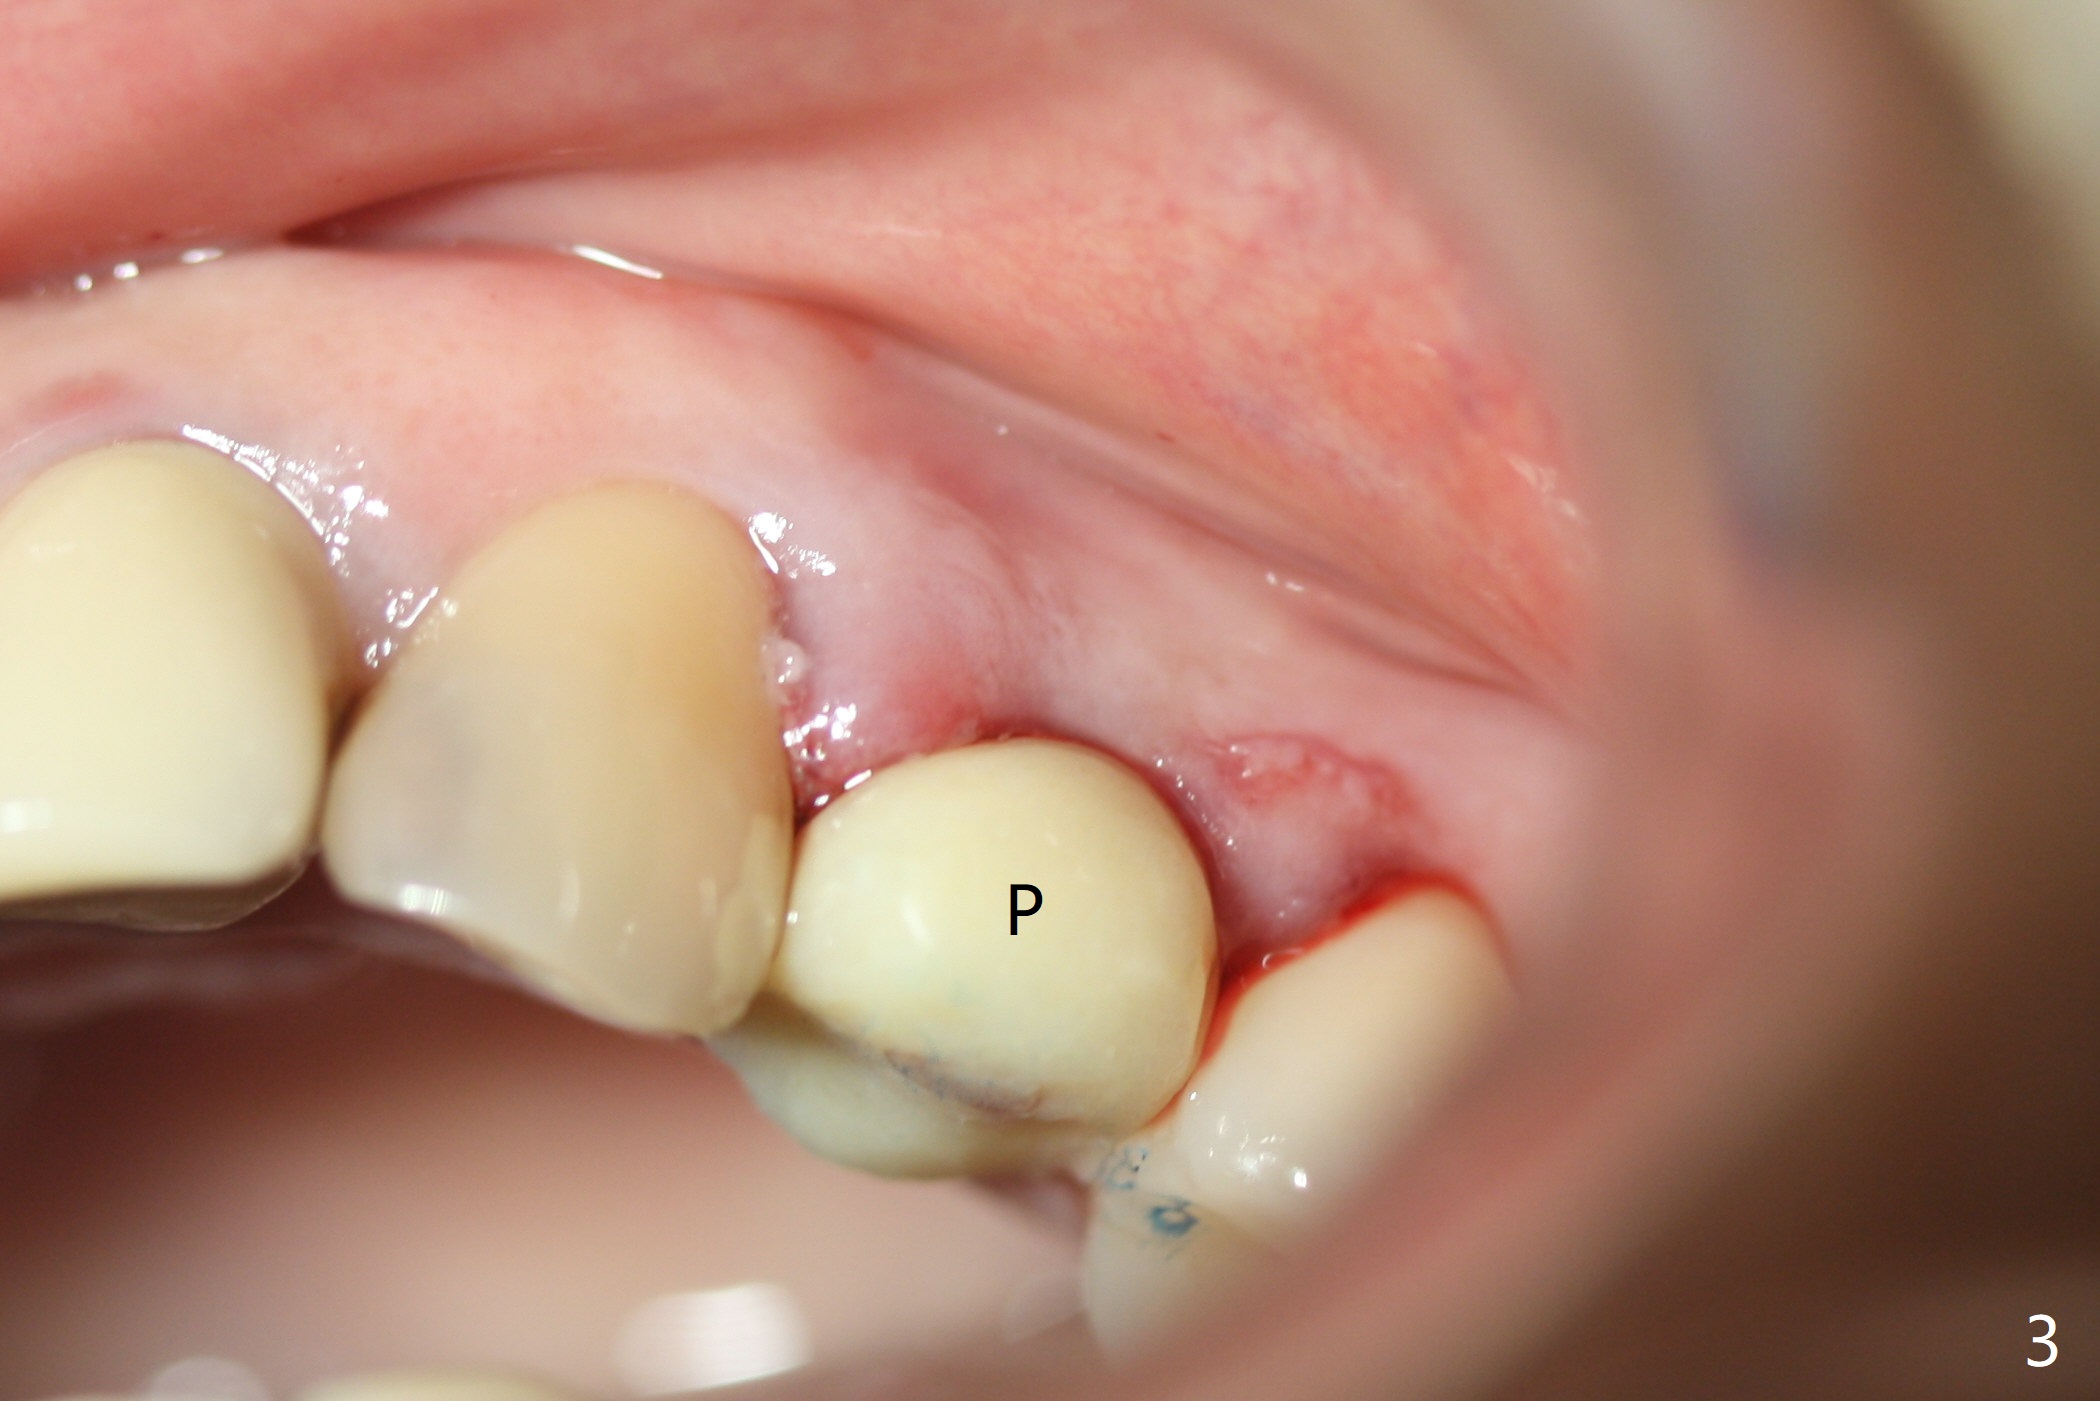

Since there is no buccal plate atrophy at 4, or 8, socket shield is not attempted at #31. Extraction turns out to be difficult because of tooth fracture. The buccal and palatal flaps have to be elevated minimally for tooth sectioning and purchase point formation. More surprising, a 4.5 mm implant appears to be too wide for the space; a 4x17 mm implant achieves insertion torque >60 Ncm (Fig.1,2). In fact Vanilla graft is placed before and after implantation. The advantage of bone graft before implant is that the graft is able to be placed as apical as possible to repair the apical defect if it is present. The disadvantage is hemorrhage. After placement of a 3.5x5 mm abutment, an immediate provisional is fabricated (Fig.3 P), which seems to be able to hold the separated buccal papillae in place. The latter heal around the immediate provisional 9 days postop (Fig.4). Because of the seal, the bone graft remains in place 1 month postop (Fig.5). There is no bone loss 5.5 months postop (Fig.6,7) or 6.5 months postop (immediately post cementation, Fig.8).